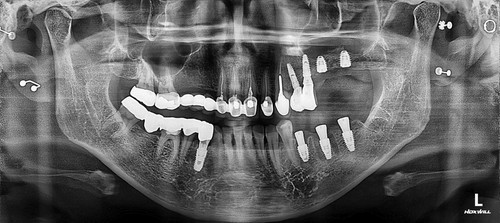

저희 치과에 오신 거는 발치한 날로부터 약 3주가 지난 상태로 오셨는데 발치한 치과에서는 한달이 안 되었기 때문에 더 기다려 볼 것을 권유 받으셨었습니다. 그런데 환자분이 제가 구강상악동누공에 대하여 작성한 포스팅을 보시고 저희 치과를 방문하시게 되었습니다. 보통 발치한지 3주가 되면 구강상악동천공의 단계를 지나서 구강상악동누공의 상태로 발전하게 됩니다. 내원 당시에 찍은 시티에서 10mm 이상의 천공이 확인 되었고 막아 놓았던 비흡수성 차례막을 제거하니 자연 치유될 정도의 천공이 아닌 걸로 확인하고 상악동누공폐쇄술을 시행하기로 하였습니다.

보통 5mm보다 작은 천공은 상악동염증이 없는 경우에는 자연치유 된다고 주장하는 논문도 있고 3mm 보다 작은 천공은 자연치유 된다고 말하는 논문도 있습니다. 하지만 제가 현재까지 약 30명 가량의 상악동누공폐쇄술을 했는데 환자 중에서 4mm 정도의 천공이 자연치유되지 않아서 폐쇄술을 한 경우도 2명 정도 있었습니다. 이걸로 보아서 5mm 보다는 3mm 보다 작은 천공이 자연치유 된다는 주장이 더 합당하다고 생각됩니다. 그래서 이 환자분은 10mm 이상의 매우 커다란 천공이 있었기 때문에 반드시 폐쇄술을 시행해 주어야 하지만 잇몸 상태가 너무 안 좋아서 잇몸이 어느 정도 치유될 때까지 기다린 후에 상악동누공폐쇄술을 계획하였고 성공적으로 잘 막혔습니다.

상악동누공폐쇄술이 성공하면 그 다음 단계로는 치조골 이식과 임플란트 식립을 해야 하는데 간혹가다 일반적인 상악동거상술에 비하면 누공이 있었던 부위는 상악동점막과 잇몸살이 유착되어서 힘든 경우가 많습니다. 물론 폐쇄술을 시행하면서 상악동에 뼈이식을 동시에 하는 것도 하나의 방법이 될수 있겠으나 성공했을 때 뿐만 아니라 누공폐쇄술이 실패했을 때를 가정한다면 통상적으로 동시 뼈이식을 시행하기에는 다소 위험성이 따르는 것이 사실입니다. 그래서 이 환자분은 안전하게 단계적으로 진행하기로 하였으며 누공폐쇄술이 성공한 후에 상악동 측방거상술을 시행하였고 이식한 뼈가 충분히 굳은 후에 임플란트를 식립하였습니다.